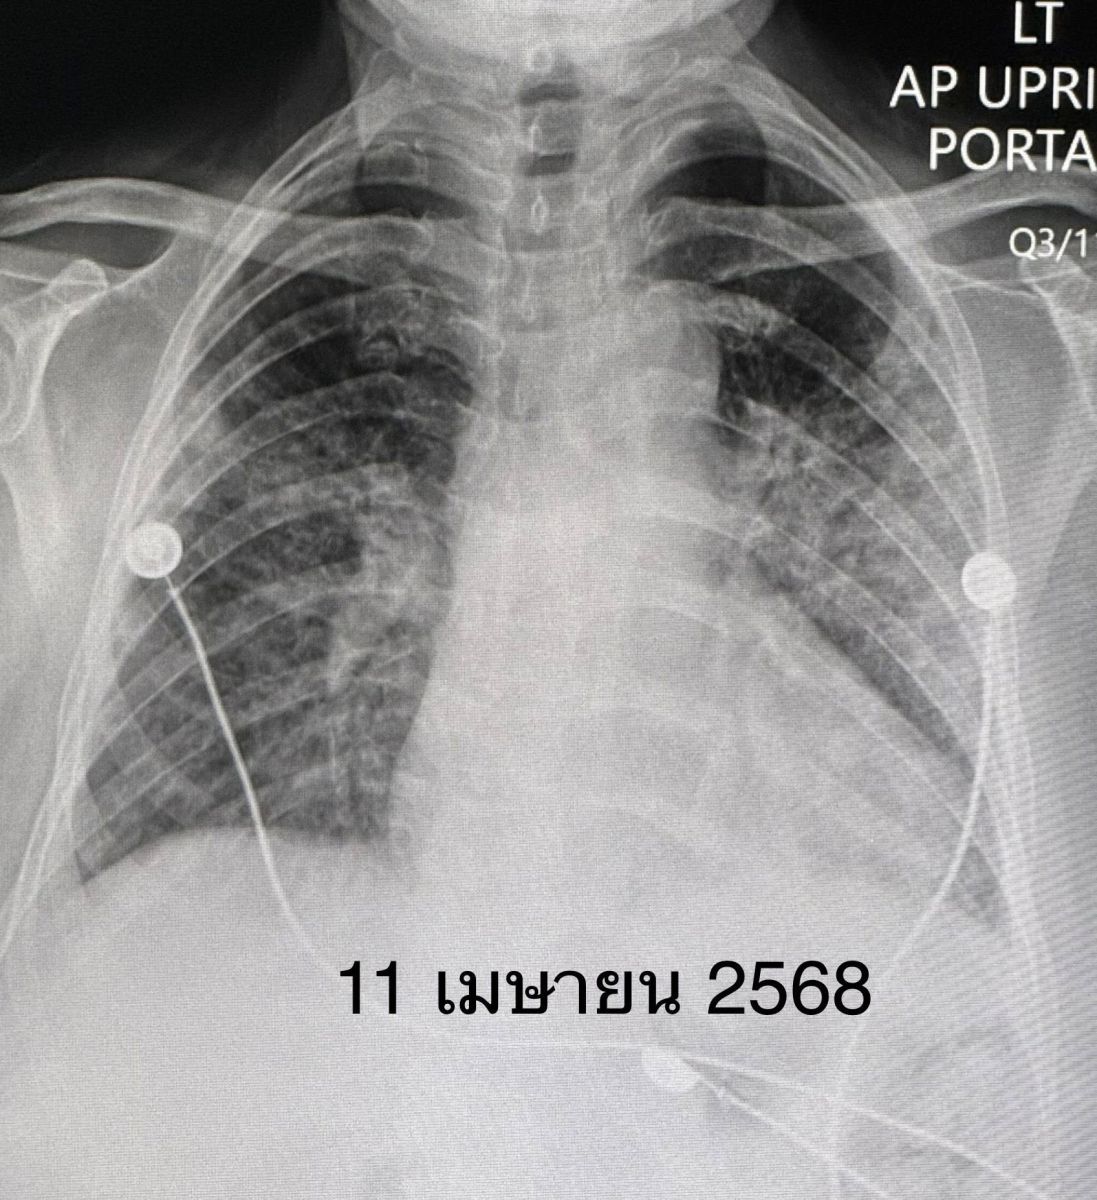

วันที่ย้ายมา หลังจากซักประวัติ ตรวจร่างกาย และทบทวนประวัติเดิม ก็ทำให้คิดถึงโรคภูมิต้านทานตนเอง (Autoimmune Diseases) ทำให้เกิดโรคเนื้อเยื่อปอดอักเสบ หรือ Interstitial lung disease (ILD) มากที่สุด ส่งเลือดตรวจพบ Anti MDA5 และ Anti-Ro52 บวก ค่า Ferritin สูง ค่า CPK ของกล้ามเนื้อปกติ ค่าเอนไซม์ของตับสูงเล็กน้อย ค่าไตปกติ ระดับโซเดียมในเลือดต่ำเกิดจาก Syndrome of inappropriate ADH

สรุปแล้วผู้ป่วยรายนี้เป็นโรคภูมิต้านทานตัวเองชนิด Anti-MDA5 antibody positive dermatomyositis ทำให้เนื้อเยื่อปอดอักเสบ และปอดเกิดพังผืดอย่างรวดเร็ว ไม่มีกล้ามเนื้ออ่อนแรง ไม่มีความผิดปกติของผิวหนัง ให้ยาสเตียรอยด์ชนิดฉีดขนาดสูง ต่อมาเปลี่ยนเป็นชนิดกิน ยากดภูมิคุ้มกันไมโคฟีโนเลต ยาไฮดรอกซีคลอโรควิน และยา Tolvaptan รักษาโรคโซเดียมในเลือดต่ำ